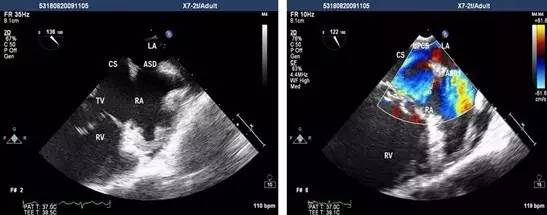

经食管超声心动图是将超声探头置入食管内,从心脏的后方向前近距离探查其深部结构,避免了胸壁、肺气等因素的干扰,故可显示出清晰的图像,提高对心血管疾病诊断的敏感性和可靠性。

为什么经食道超声心动图就能发现心房血栓呢?因为食管位于左心房后面,绝大部分人食管与左房后壁都有接触。

通过食管置入超声探头,就能很直观的从左心房后面看到心房里面的结构,能够看清心房、心耳内有无血栓。

而如果使用普通经胸的心脏彩超看心房,超声波需要穿过皮肤、肌肉、骨骼、肺等组织,就很难分辨清楚心房内有无血栓。